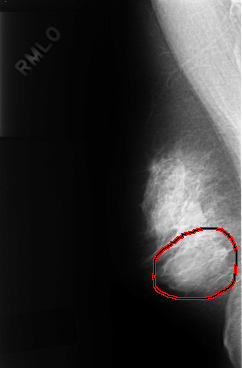

FILE: C_0324_1.RIGHT_MLO.OVERLAY

TOTAL_ABNORMALITIES 1

ABNORMALITY 1

LESION_TYPE MASS SHAPE LOBULATED MARGINS OBSCURED

ASSESSMENT 3

SUBTLETY 4

PATHOLOGY BENIGN

TOTAL_OUTLINES 1

BOUNDARY